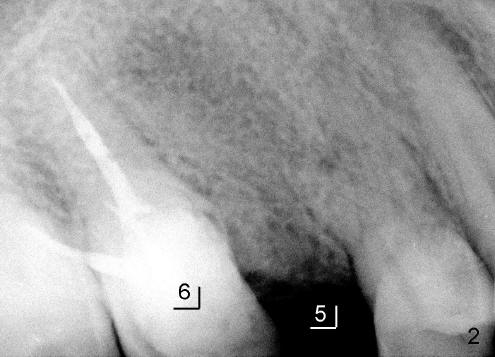

颊舌侧骨头宽度也很充足,所以使用钻头形成植牙床(图三:三点五乘十七毫米钻头(D)),之后植入四点五乘十七毫米种植体(图四),其实一个植牙花的时间比两个还长,为什么?